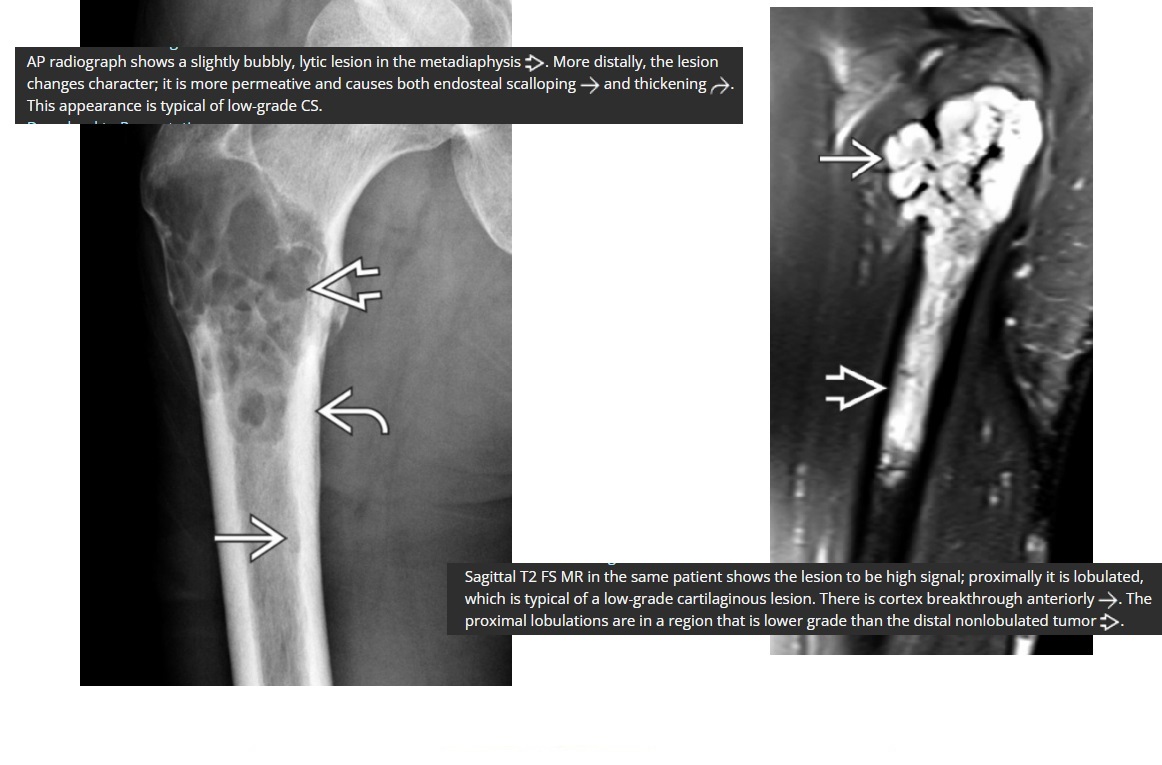

Chondrosarcoma

May be cecondary to

- Osteochondromas

- enchondromas

Chondrosarcomas occur in the pelvis, femur, humerus.

Skull base, TMJ

DDX

-Most well differentiated, low grade = ‘low grade chondroid lesion’ , cant differentate from enchondroma

-Bone infarct

MRI

Lobular growth

High 2 signal/STIR, low T1

ring and arcs/chondroid matrix islands on CT

Soft tissue extension

**endosteal scalloping. **

if no mineralized matrix/rings and arcs = aggressive/high grade

How to tell chondrosarcoma from enchondroma ?

* Pathological fracture occurring with minimal trauma

* Multilayered or spiculate periosteal reaction

* Permeative or moth-eaten osteolysis

* Cortical destruction

* A soft tissue mass

Endosteal scalloping more than 2/3 cortex